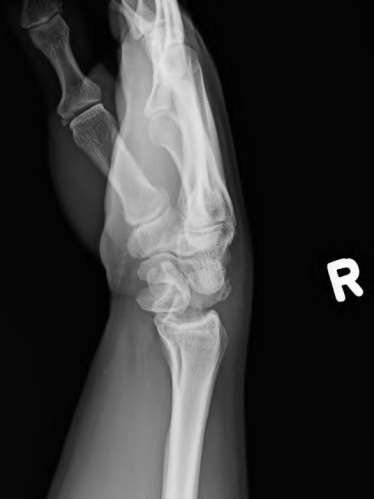

A 35-year-old woman reports wrist pain after a fall onto an outstretched hand. On exam, she has focal tenderness over the wrist snuffbox. A radiograph and CT image are shown in Figures A and B. What is the proper treatment of her injury?